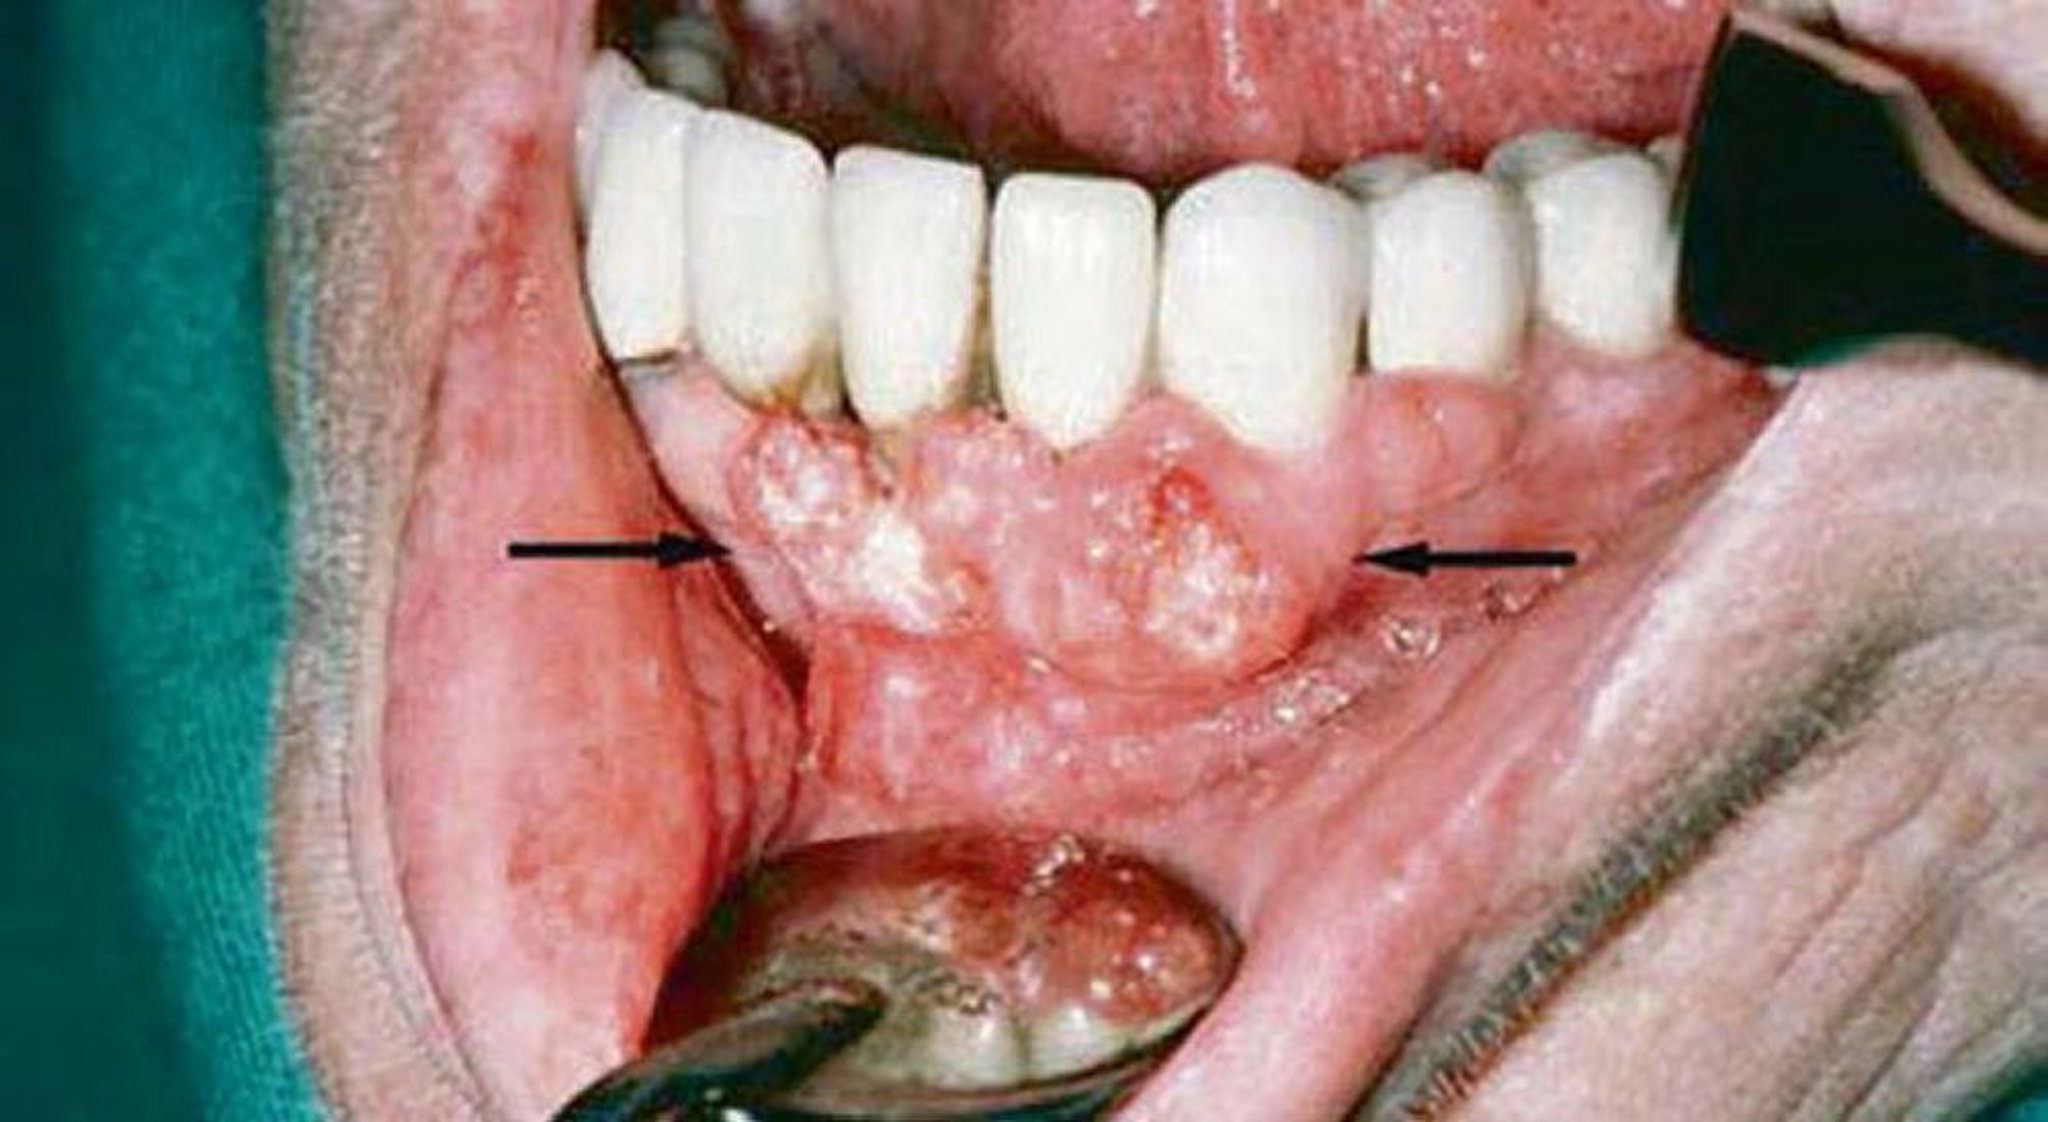

Плоскоклітинна карцинома (ураження ясен)

Gingival examination of this patient showed evidence of squamous cell carcinoma. Imaging studies showed invasion of the mandible.